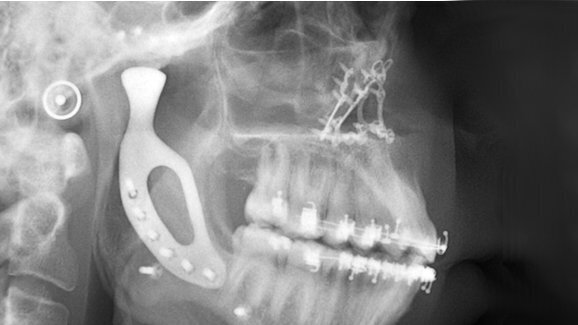

MELBOURNE – Een jonge Australiër heeft een unieke kaakgewricht-prothese gekregen: de ‘kunstkaak’ van titanium is vervaardigd met een 3D-printer. Mond-, kaak- en aangezichtschirurgen van de Universiteit van Melbourne werkten samen met medische ingenieurs om het temporomandibulaire gewricht te maken en plaatsen.

Patiënt Richard Stratton werd geboren met condylaire hypoplasie, waardoor het temporomandibulaire gewricht zich niet ontwikkelde. Hierdoor groeide de linkerzijde van zijn kaak – en daarmee van zijn gezicht – veel minder dan rechts. Stratton kreeg problemen met zijn kaakbeweging, kon slecht kauwen en had moeite met fysieke gezichtsuitdrukkingen.

Stratton kreeg in een flinke operatie een titanium prothese geplaatst om zijn kaak te herstellen. De prothese werd gemaakt met behulp van de nieuwste methode om metaal in 3D te printen, ontwikkeld door het Australische 3D Medical. Door het te printen, kon de prothese precies op maat worden gemaakt.

Volgens de artsen zien de eerste resultaten van Strattons operatie er goed uit: zowel klinisch als biomechanisch werkt de gewrichtsprothese naar behoren. Het team hoopt dat met deze techniek steeds meer mensen een dergelijke gespecialiseerde en op maat gemaakte prothese kunnen krijgen.